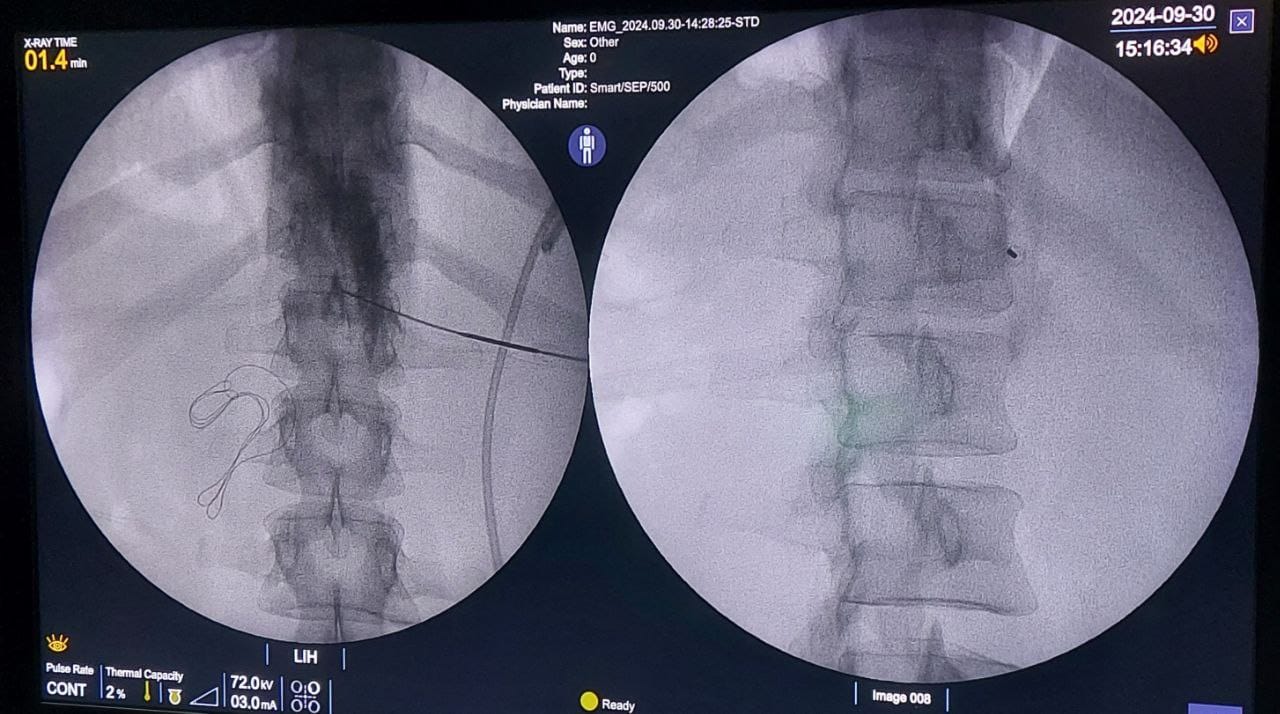

Procedures